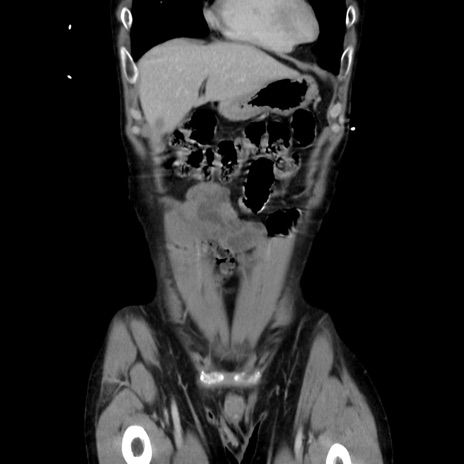

症例37(冠状断像)

【症例】40歳代 男性

【主訴】腹痛

【現病歴】4時間ほど前に電車に乗車中に臍部上より腹痛出現。徐々に増悪し起立困難となり、救急外来受診。生ものは数日食べていない。今朝お雑煮を食べた。

【身体所見】BT 36.8℃、BP 117/84mmHg、HR 91/min、SpO2 97%、苦悶様、腹部:臍上部広範囲圧痛あり、反跳痛±

【データ】WBC 8100、CRP 0.03